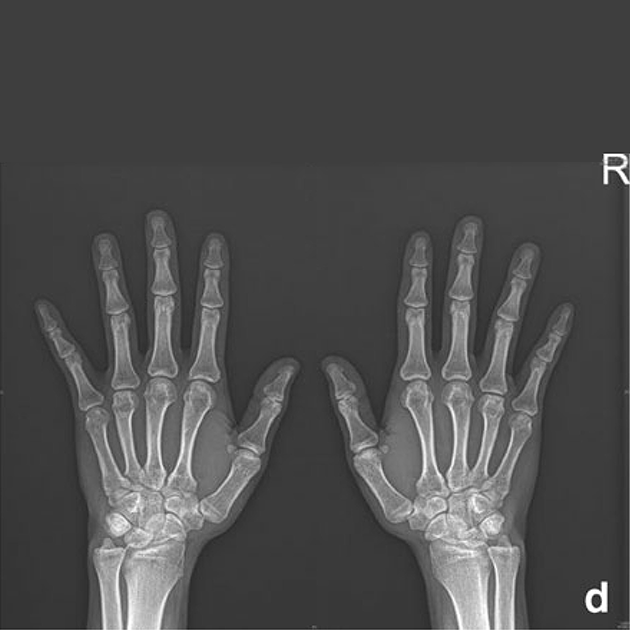

Manifestaciones de disostosis múltiple en las manos. La radiografía muestra las manos de un paciente con MPS en la niñez, con afilamiento proximal moderadamente severo y metacarpianos expandidos con cortezas delgadas.

Reproducido con permiso de Lachman, J Pediatr Rehabil Med, 2010.